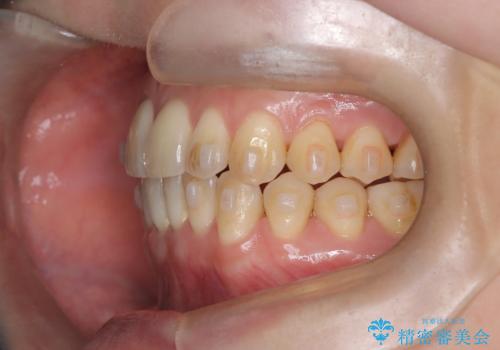

- 「下の前歯が斜めになっている」を主訴に来院された患者様です。

下顎前歯に叢生があり、右上2は反対咬合の状態でした。

下顎前歯の叢生がとれ右上2の反対咬合も改善し患者様にも満足していただけました。治療期間は1年~1年半を見込んでいましたが、患者様の協力もあり10か月で矯正を終えることが出来ました。